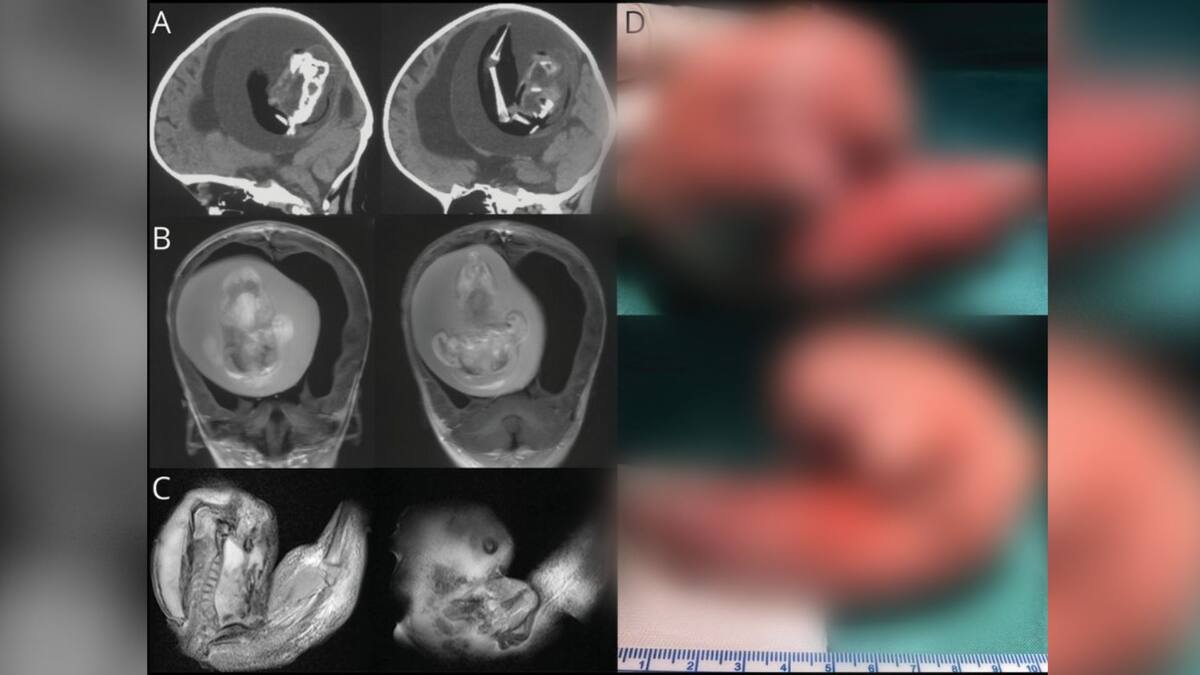

Lo que parecía ser una hidrocefalia en una pequeña de tan solo 1 año terminó siendo una sorpresa para los padres, los médicos y para el mundo entero.

Los problemas motores, el no poderse sentarse y el constante crecimiento de su cabeza que ya llegaba a las 56 centímetros se lo achacaban a la enfermedad neurológica. Sin embargo, para los padres la preocupación aumentaba y la llevaron hasta un centro asistencial donde le realizaron el chequeo médico y análisis de rutina.

El resultado: existía una masa anormal al interior de su cabeza y esta poseía huesos.

El caso fue reseñado por especialistas de la revista especializada Neurology de la Academia Americana de Neurología en un artículo científico. Todas las afectaciones que sufría la menor eran consecuencias de un feto que estaba dentro de su cráneo y, de hecho, ya había desarrollado extremidades superiores, uñas y más.

A este atípico caso se le denomina 'fetus in fetus' donde en el útero se fusionan los dos fetos y uno de ellos crece dentro del otro, en este caso la madre de la niña, originarios de China, que esperaba gemelas solo tuvo a uno y la otra se alojó en la cabeza de su hermana.

'Se propone que el 'fetus in fetus' intracraneal surja de blastocitos no separados. Las partes unidas se desarrollan en el cerebro anterior del feto huésped y envuelven al otro embrión durante el plegamiento de la placa neural', señaló el doctor Chunde Li, del Hospital Tiantan de Beijing en su publicación médica.

El extraño y poco común fenómeno se extendió por un año hasta la extirpación del feto que se había convertido en un parásito evitando la muerte de la niña. Durante ese periodo de tiempo compartieron sangre y como crecía, aumentaba la presión sobre el cerebro de la bebé causándole los síntomas mencionados.